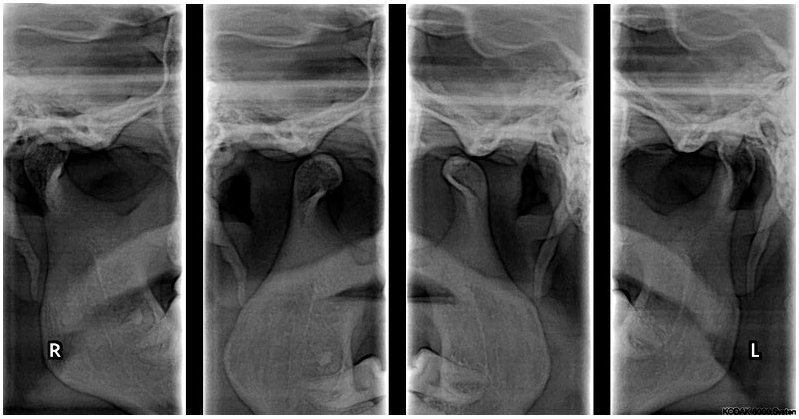

Radiografía A.T.M. Posteroanterior

A.T.M. Posteroanterior

La vista posteroanterior permite evaluar:

• Simetría de ambas articulaciones

• Movimientos laterales de la mandíbula

• Asimetrías faciales o mandibulares

• Problemas de desarrollo mandibular